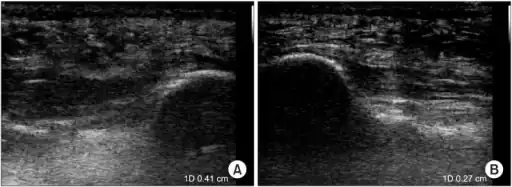

a)Ultrasonographic finding of plantar fasciitis b)normal sonographic finding

a)Ultrasonographic finding of plantar fasciitis b)normal sonographic finding Heel bone with heel spur

Heel bone with heel spur Thickened plantar fascia in ultrasound

Thickened plantar fascia in ultrasound

The plantar fascia has three fascicles-the central fascicle being the thickest at 4 mm, the lateral fascicle at 2 mm, and the medial less than a millimeter thick.[18] In theory, plantar fasciitis becomes more likely as the plantar fascia's thickness at the calcaneal insertion increases. A thickness of more than 4.5 mm ultrasound and 4 mm on MRI are useful for diagnosis.[19] Other imaging findings, such as thickening of the plantar aponeurosis, are nonspecific and have limited usefulness in diagnosing plantar fasciitis.[13]